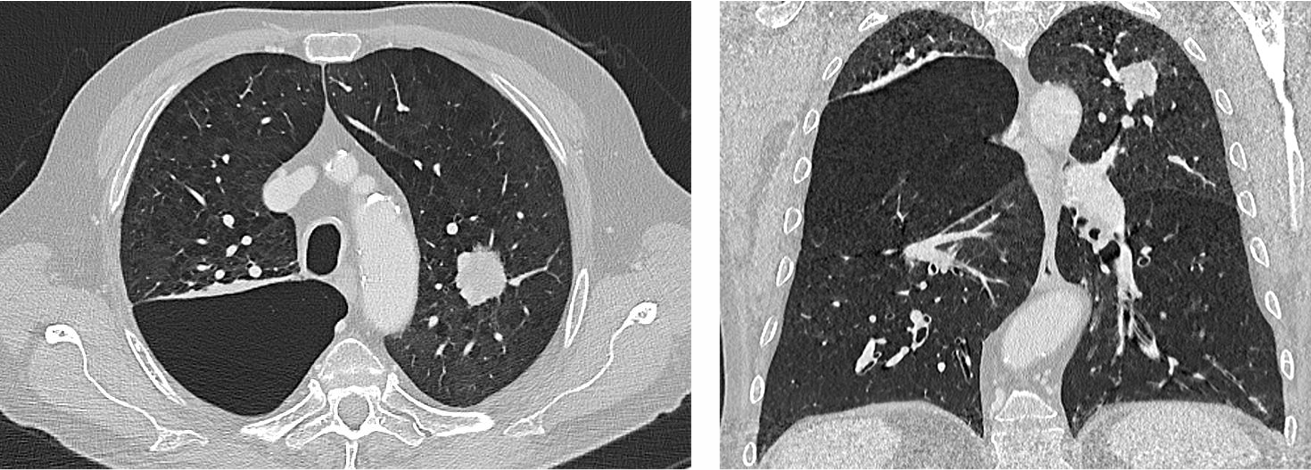

CT随访(2025年5月,放疗后18个月):原左上肺病灶明显缩小,呈纤维化及放疗后改变,未见明确的肿瘤复发迹象。

PET/CT随访(2024年6月,放疗后18个月):

与治疗前(SUVmax 19.8)相比,复查PET显示原病灶处未见异常FDG代谢,提示完全代谢缓解。